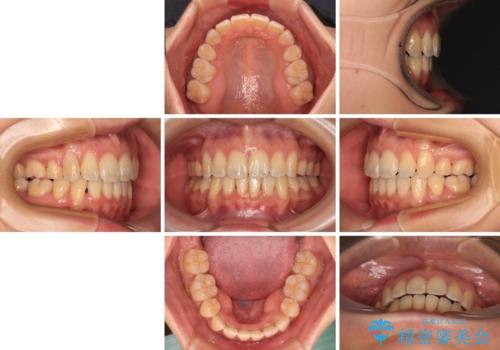

- 前歯の出っ歯と口元の閉じにくさを気にして来院された患者様です。

口元を積極的に引っ込めるために、上下左右の小臼歯4本を抜歯し、目立たないワイヤー装置にて矯正治療を行うこととしました。

上下前歯の歯軸の角度が大きく改善され、お口を閉じたときに顎先に認められた梅干し様の皺も改善されました。